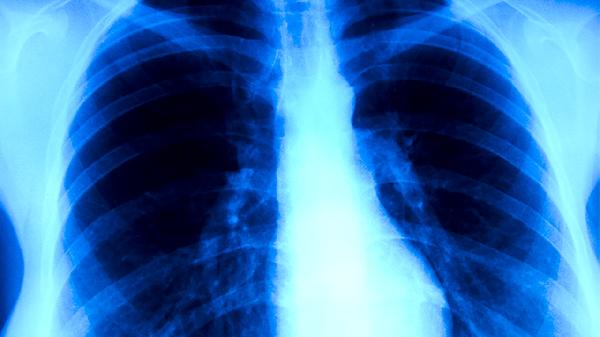

食疗期间应保持每日摄入优质蛋白60-80克,如鸡蛋、鱼肉、豆制品等,配合维生素A丰富的胡萝卜、菠菜等深色蔬菜。居住环境需定期通风换气,避免去人群密集场所。出现持续咳嗽、痰中带血、午后潮热等典型症状时,须立即进行结核菌素试验和胸部影像学检查。确诊患者应严格遵循抗结核药物治疗方案,完成6-9个月规范疗程。